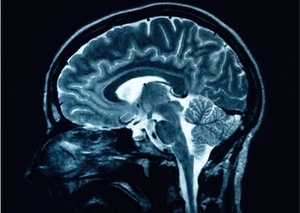

Did you know a 6-year study showed that people over 55 with low vitamin D levels are 60% more likely to suffer from substantial cognitive decline than those with adequate levels of the nutrients.